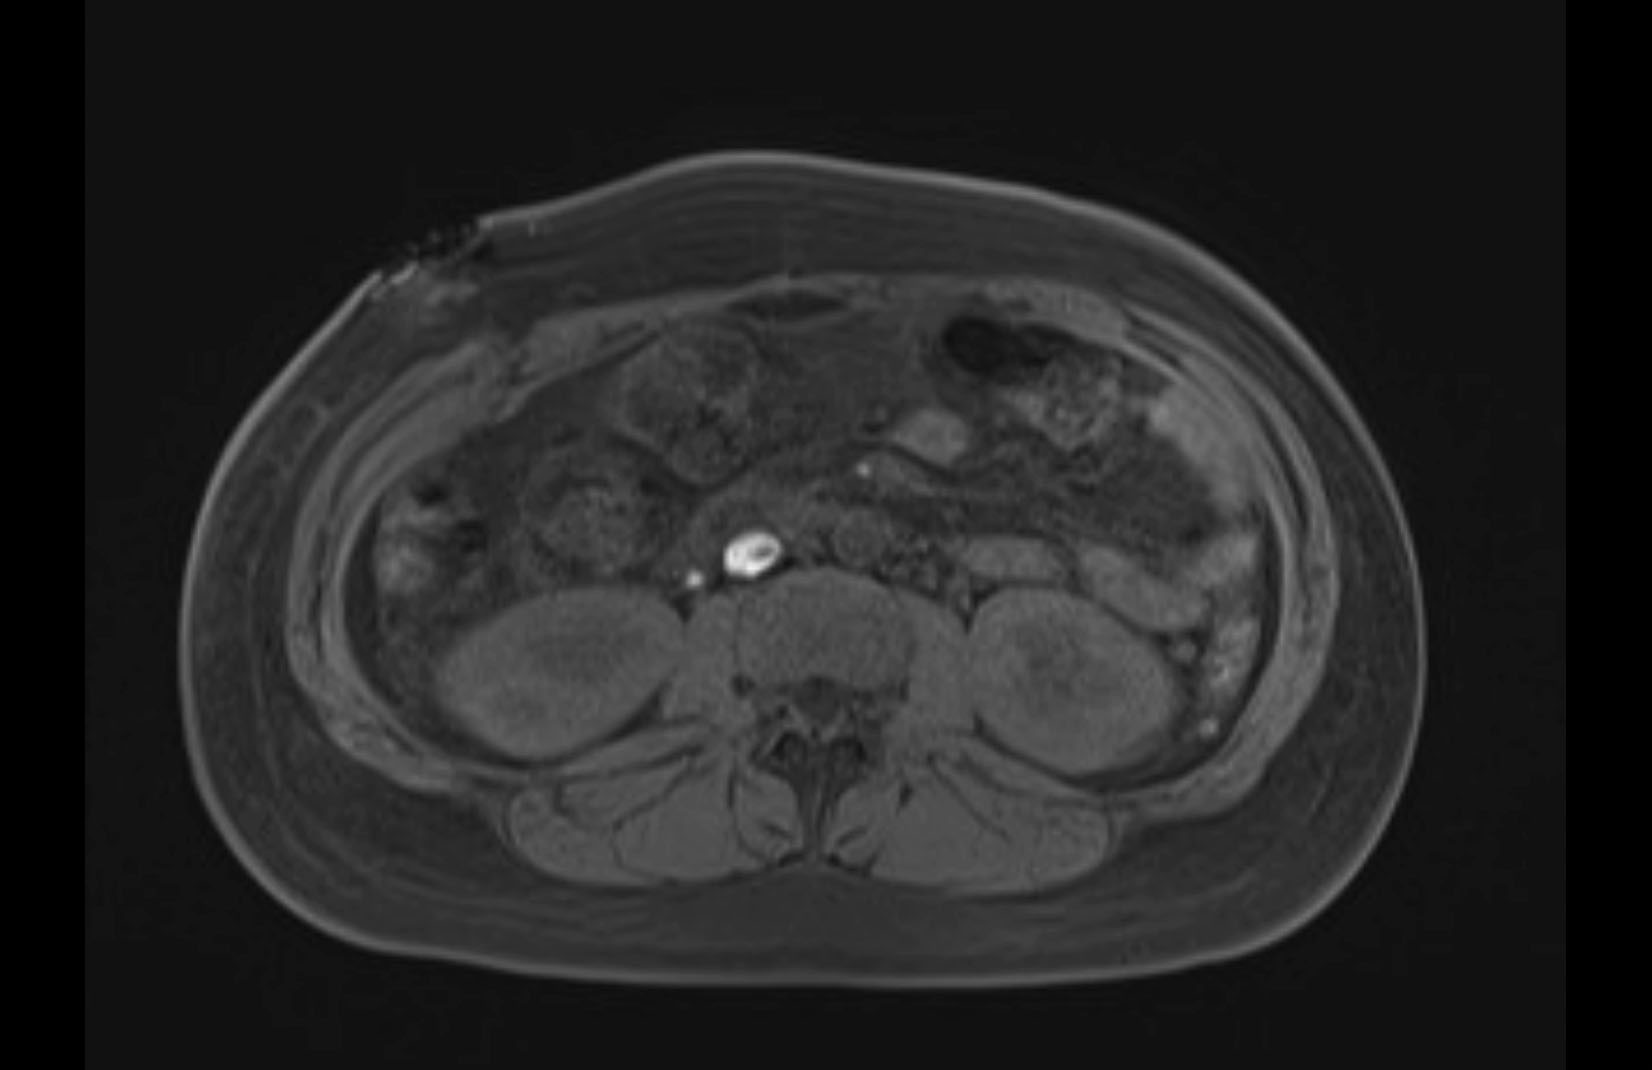

MRI T2

Imaging analysis

Based on initial findings, which issue(s) would you be most concerned about?